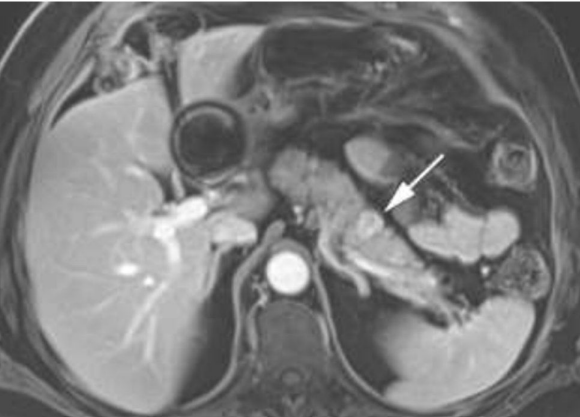

Mulher 57 anos. Dor epigástrica leve e dispepsia há 3 meses. Realizou USG que mostrou lesão mal definida em cauda pancreática. Após avaliação cirúrgica, fez uma RM do abdome superior sugestiva de tumor neuroendócrino pancreático (PNET) de 3,8 cm (Imagem abaixo). EDA normal. Sem sintomas de disglicemia ou diarreia.

Em relação à conduta e diagnóstico (estadiamento), assinale a alternativa CORRETA.